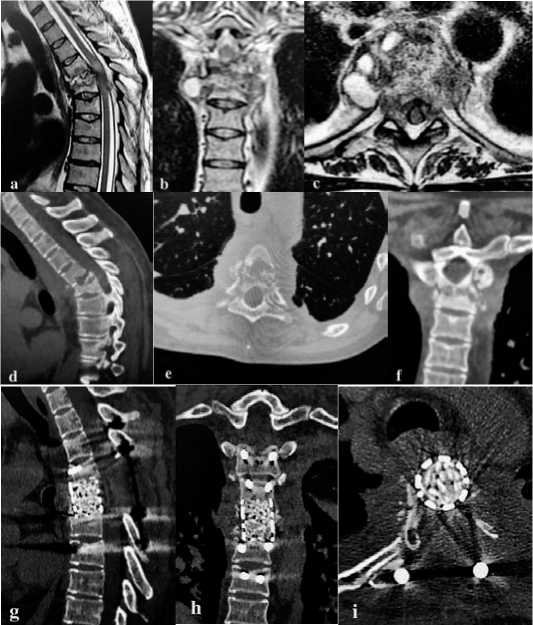

Рисунок 4 . Результаты обследования до и после хирургического лечения. а, b, c – компьютерные томограммы (сагиттальная проекция (а), фронтальная (b) и аксиальная (с) проекции): костная деструкция Th4-Th5 с наличием секвестров и кифотической деформации на уровне поражения; d, e – кон трольные компьютерные томограммы сразу после операции в сагиттальной (d) и аксиальной (e) проекции; f, g – контрольные компьютерные томограммы через 8 месяцев после операции в сагиттальной (f) и аксиальной (g) проекции: определяется интеграция и перестройка аутокостной крошки, хорошо выражена оссификация по переферии кейджа (Grade I по Eck et al)

Рисунок 3 . Результаты обследования до и после хирургического лечения. а, b, c – магниторезонансные томограммы (сагиттальная проекция (а), фронтальная (b) и аксиальная (с) проекции): определяется гнойный спондилит Th5-Th6 позвонков с паравертебральными абсцессами, со сдавлением спинного мозга и присутствием очага миелоишемии; d, e, f - компьютерные томограммы в сагиттальной (d), аксиальной (e) и фронтальной (f) проекции: костная деструкция Th5-Th6 позвонков с наличием секвестров и кифотической деформации на уровне поражения; g, h, I – контрольные компьютерные томограммы в сагиттальной (g), фронтальной (h) и аксиальной (i) проекции: выполнена циркулярная декомпрессия спинного мозга, корпородез Th4-Th7 позвонков, кифотическая деформация устранена